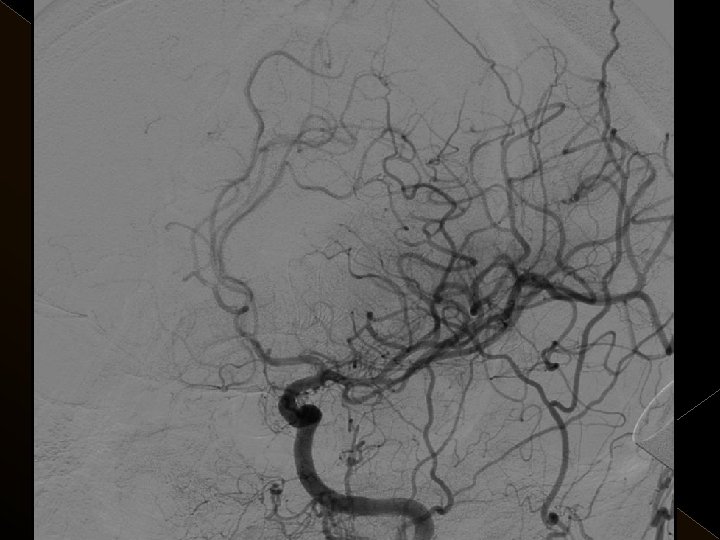

� 25 hasta (16 K, 9 E) , 27 vaskuler okluzyon � 16 orta serebral arter (MCA), � 6 baziler arter ve � 5 internal karotis arter (İCA) düzeyinde olmak üzere � Toplam 25 hasta, 27 tıkanıklığa (6 sı hariç) iv tpa sonrası endovaskuler yolla müdahale edildi

Acil servise başvuru süreleri: 1 -4. 5 saat Başvuru sırasındaki ortalama NIHSS skoru: 23 25 hastanın 21’inda kontrol serebral anjiografide tıkanıklığın tamamen açılmış olduğu görüldü. � Baziler arter ve ICA tıkanıklığı olan 4 hasta kaybedildi. � 19 hastanın 16’sında NIHSS skorlarında işlem sonrasında 24. saatte yapılan klinik değerlendirmede ortalama 10 puanlık düşüş saptandı. � � �

� İnme tedavisinde iv tpa uygulamasını takiben � intraarteriyel (İA) trombolitik tedavi (ia tpa ve ia mekanik trombolizis) � İA stent yardımı ile trombektomi yöntemleri kullanılarak tedaviye cevap ve komplikasyonlar araştırıldı.